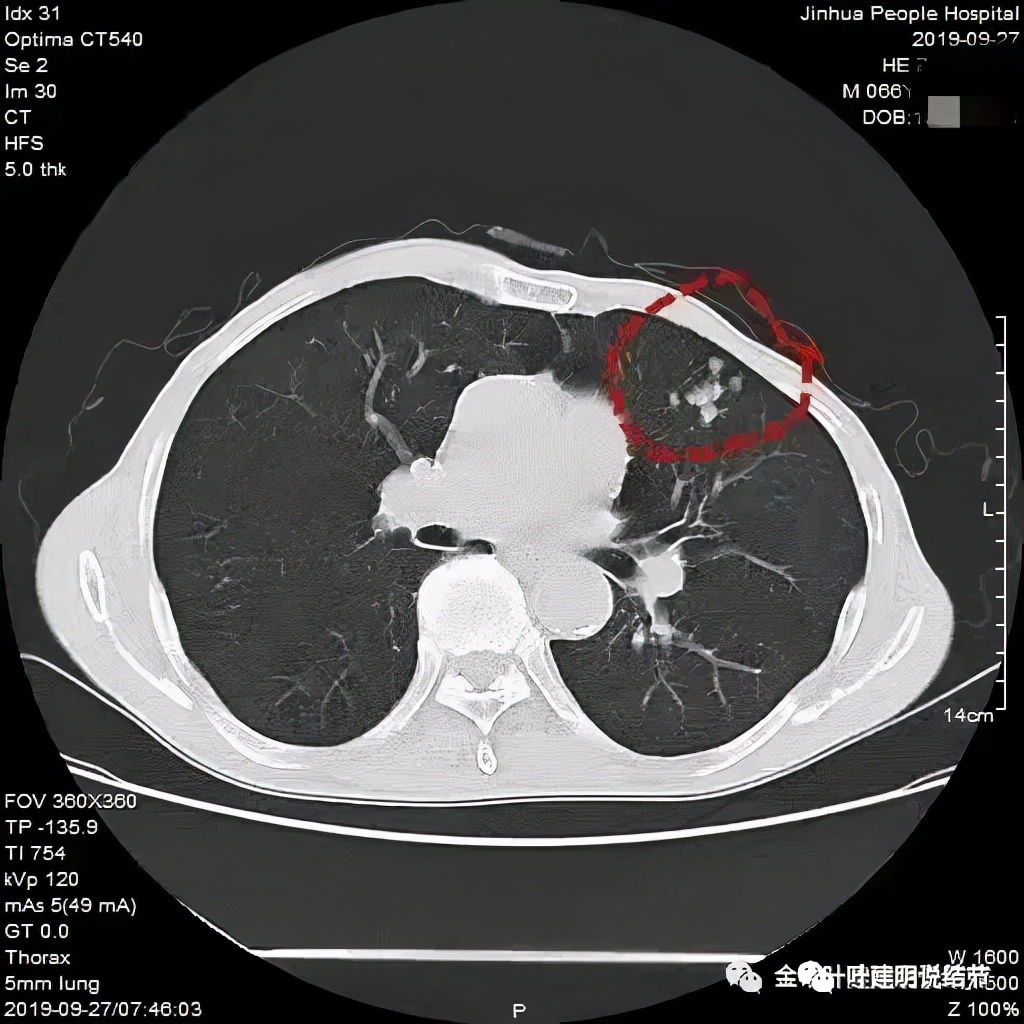

临床上我们容易见到小细胞原发灶不大,但广泛的纵隔淋巴结转移,甚至远处转移的,而且中央型多见,这时候,诊断不难。但若病灶是周围型,淋巴结肿大又不明显或不广泛,而原发灶又像这样边缘光滑的,还真倒容易误诊。之前碰到过一例小细胞肺癌是下面这样的:

左上叶簇状实性小结节,呈堆积状。开始时也没有能考虑到肺癌,是因为随访后病灶增大,经过穿刺活检确诊为小细胞肺癌。其实今天这个病例也是堆积的,也是两处病灶,只是挨的近而已。所以以后如果碰到“实性结节堆积状”的,边缘光滑缺乏收缩力或膨胀性的、周围又没有炎性渗出改变的,我们要考虑到其小细胞肺癌的可能性,而且可能性不小!